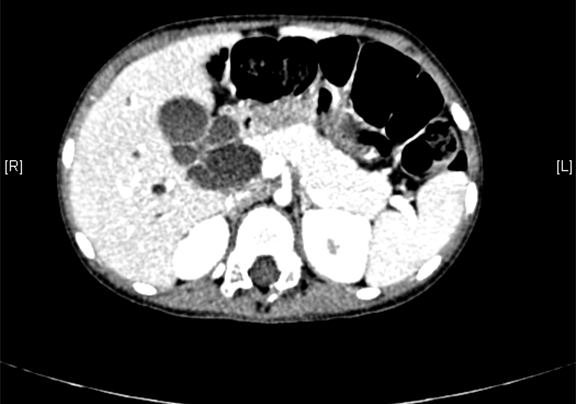

上腹部增强CT:肝内外胆管扩张,考虑先天性胆管扩张症可能性大。

术前CT检查:

静脉期